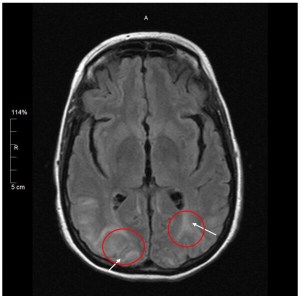

Dr. Comi stated that she saw significant brain damage on Greyson’s MRI. The areas primarily impacted was his occipital lobe and some white-matter anteriorly and posteriorly.

Dr. Comi stated that because Greyson did not fit the diagnostic criteria to be followed at the SWS clinic at Kennedy Krieger, she was going to refer us to a neurologist that handles white-matter brain diseases. Luckily, this neurologist works closely with Dr. Comi at the SWS clinic, and she vowed to help us until we could figure out what exactly was going on with our son. She handed us several lab order forms and we scheduled a follow-up with her for August 3, giving us plenty of time to get the labs done and results generated.